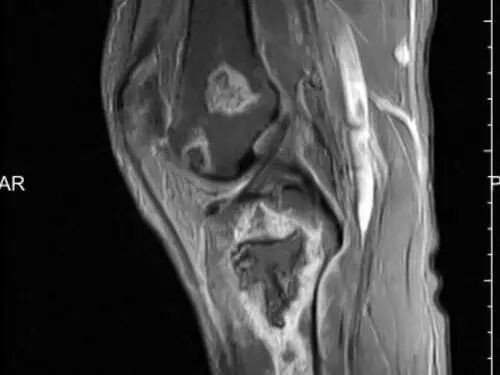

二、精准诊断:早发现结晶的“利器”

肌骨超声:无创无痛、精准度高,能清晰显示关节内结晶、滑膜增生、骨侵蚀等情况,多关节同步检查,为溶解治疗提供依据;